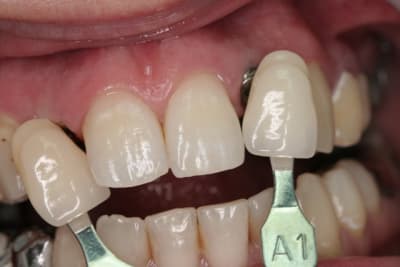

suite bis...

pose de l'implant pas simple en effet pour la 22...la corticale m'a en effet "guidé" beaucoup plus en palatin que ce que j'aurais voulu (cf pano...on à presque l'impression que je suis dans la 21...mais c'est une déformation "optique" les 2 implants ont en effet la même longueur...13mm)

photos de l'empreinte d'étude pour les autres couronnes...photos de la prise de teinte...

je sais qu'il y a une petite différence de hauteur de collet...mais les implants étant pas mal enfouis (les vis de cicat font 3mm) une petite gingivoplastie s'impose pour la 12...

le gain en expansion n'est pas faramineux...mais quand même...